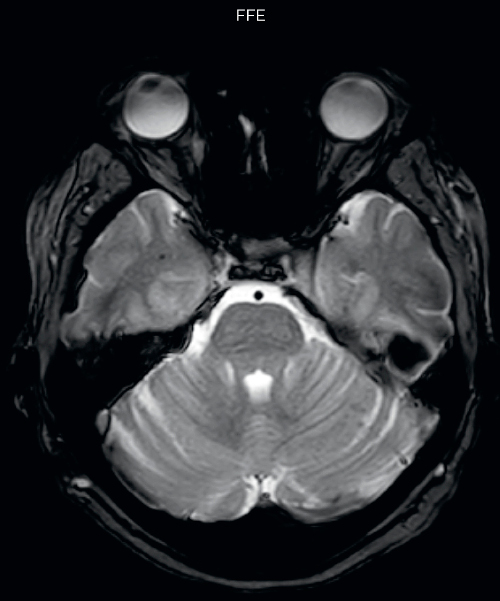

Gradient echo imaging and SWIp are compared in a patient with radiation-induced foci of hemosiderin deposition. A greater number of small foci is seen on the SWIp image. Ingenia 3.0T

“With SWIp we are basically looking for blood byproducts. It is a sensitive method for visualizing small lesions containing deoxygenated blood. In our comparison, SWIp images are vastly better than gradient echo imaging, there’s no question of that anymore.” “We find the SWIp images very useful in three areas in particular. In patients with a history of hypertension, it offers clear visualization of hemosiderin deposition from hypertensive hemorrhages. We certainly see a greater number of foci of hemosiderin deposition on the SWIp images than on the T2* gradient echo images. In addition, it also helps us visualize amyloid depositions in patients with amyloid angiopathy.” Dr. Nickerson mentions trauma patients are the third large area where SWIp is useful. “We benefit from SWIp in trauma patients, certainly in cases with diffuse axonal injury and shearing injuries. Our study shows that SWIp usually provides us better visualization,” he says. “Apart from these three, SWIp also helps us to beautifully depict the normal venous anatomy in patients with venous outflow issues or vascular congestion. In some cases, we have seen downstream effects of arterial problems. And in patients with vascular malformations we have seen deposition of blood products associated with those.”

“We switched over entirely. SWIp is now included in all our routine brain exams. We developed two different SWIp sequences: a high spatial resolution (0.5 x 0.5 mm) version that takes 5.5 minutes and our fast SWIp that takes just three minutes. Only in patients that are moving tremendously we occasionally still acquire a gradient echo sequence.” “For us, SWIp use has resulted in more diagnostic confidence when small lesions, such as small shear injuries, vascular malformations, or minute amounts of calcification, need to be detected,” says Dr. Nickerson. “Our physicians greatly value the SWIp images. When we get patients transferred from other facilities with SWIp missing from their exam, we have several neurologists and neurosurgeons who order a new MRI exam because they want to see the SWIp images.”